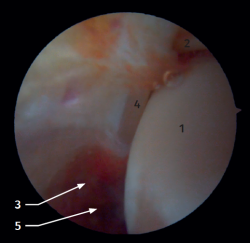

Visión artroscópica anterior

El 20% del LTPA es intraarticular(7). Cuando realizamos un acceso anteromedial del tobillo dirigiendo el artroscopio hacia lateral podemos ver las fibras distales del LTPA con su disposición oblicua y su continuación con el ligamento peroneo-astragalino anterior (Figura 2). Si avanzamos dentro de la articulación tibioastragalina, veremos la articulación tibioperonea distal con el receso sindesmal ocupado de tejido sinovial (Figura 3).

Figura 2. Visión artroscópica anterolateral del tobillo derecho. 1: cúpula astragalina; 2: cara anterior de la tibia; 3: peroné; 4: fibras distales del ligamento tibioperoneo anterior; 5: ligamento peroneo-astragalino anterior.

Figura 3. Visión artroscópica anterolateral de un tobillo derecho al introducirnos en la tibioastragalina. 1: cúpula astragalina; 2: cara articular de la tibia; 3: peroné; 4: articulación tibioperonea distal; 5: fibras distales del ligamento tibioperoneo anterior.